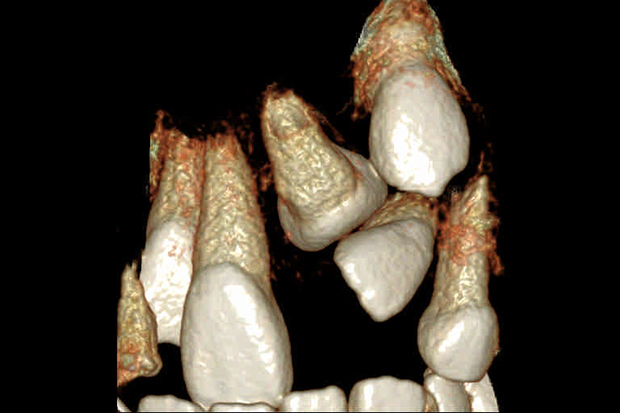

【埋伏歯】下顎前突 小児矯正 表側マルチブラケット装置

| 主訴 |

上の歯が出てこない 受け口 |

||

|---|---|---|---|

| 診断名 |

上顎左側中切歯、側切歯の埋伏歯および側切歯、犬歯の移転歯を伴う反対咬合 |

||

| 年齢 | 8歳 | 性別 | 女子 |

| 治療に用 いた装置 |

舌側弧線装置 唇側マルチブラケット装置 (メタルワイヤー) | 抜歯部位 | 非抜歯 |

| 治療期間 ・回数 |

3年10か月・46回 | 治療費 概算 |

約40万円 (調整料を含む) |

| 治療内容 詳細 |

前歯が生えてこないのをかかりつけの歯科医院にて指摘され、ご紹介された患者様です。虫歯も多い子でしたが、虫歯の治療、管理も同時に行い、小児矯正だけで綺麗に治りました。 |

||

| リスク・ 副作用 |

装置による違和感 疼痛 虫歯のリスクなど |

||